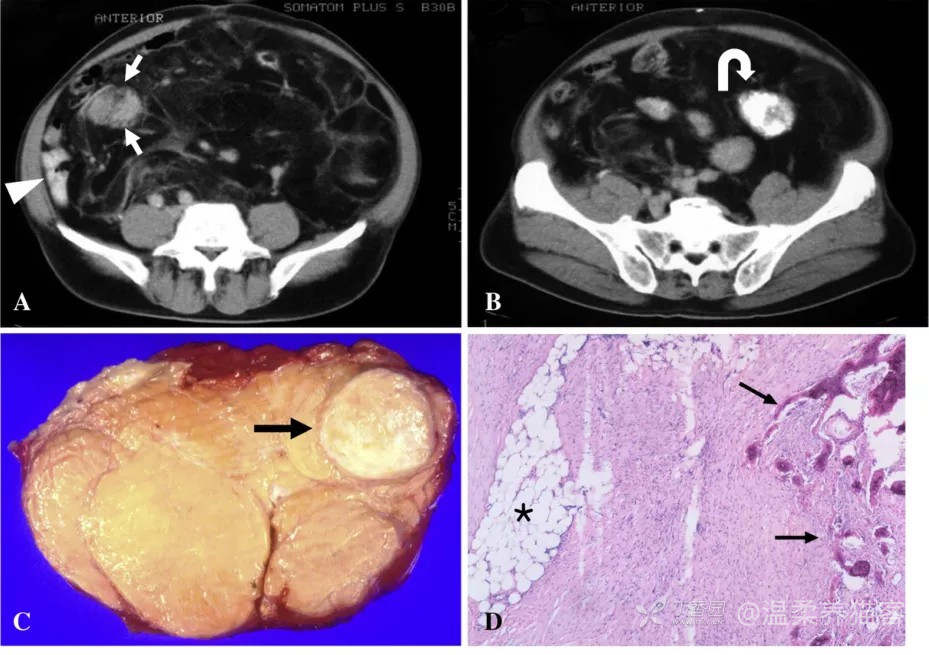

图 1Hong S H, et al. Clinical imaging, 2010, 34(3): 203-210.

图片来源:Hong S H, et al. Clinical imaging,2010,34(3): 203-210.

57 岁男性,腹膜后 DDL 伴多形性 MFH-样肉瘤和骨肉瘤灶

(A、B) CT 增强可见巨大脂肪成分的肿块。肿块内可见数个定义不清的软组织肿块、强化均匀且可见明确的骨成分 (B 图曲线箭头)。髂血管因巨大肿块向右侧偏曲。

(C) 手术标本横切面显示脂肪块,内部有明确的骨成分 (箭头)。

(D) 显微照片 (HE 染色,原始放大倍率 ×4) 显示脂肪肉瘤 (*) 伴骨肉瘤灶 (箭头)。